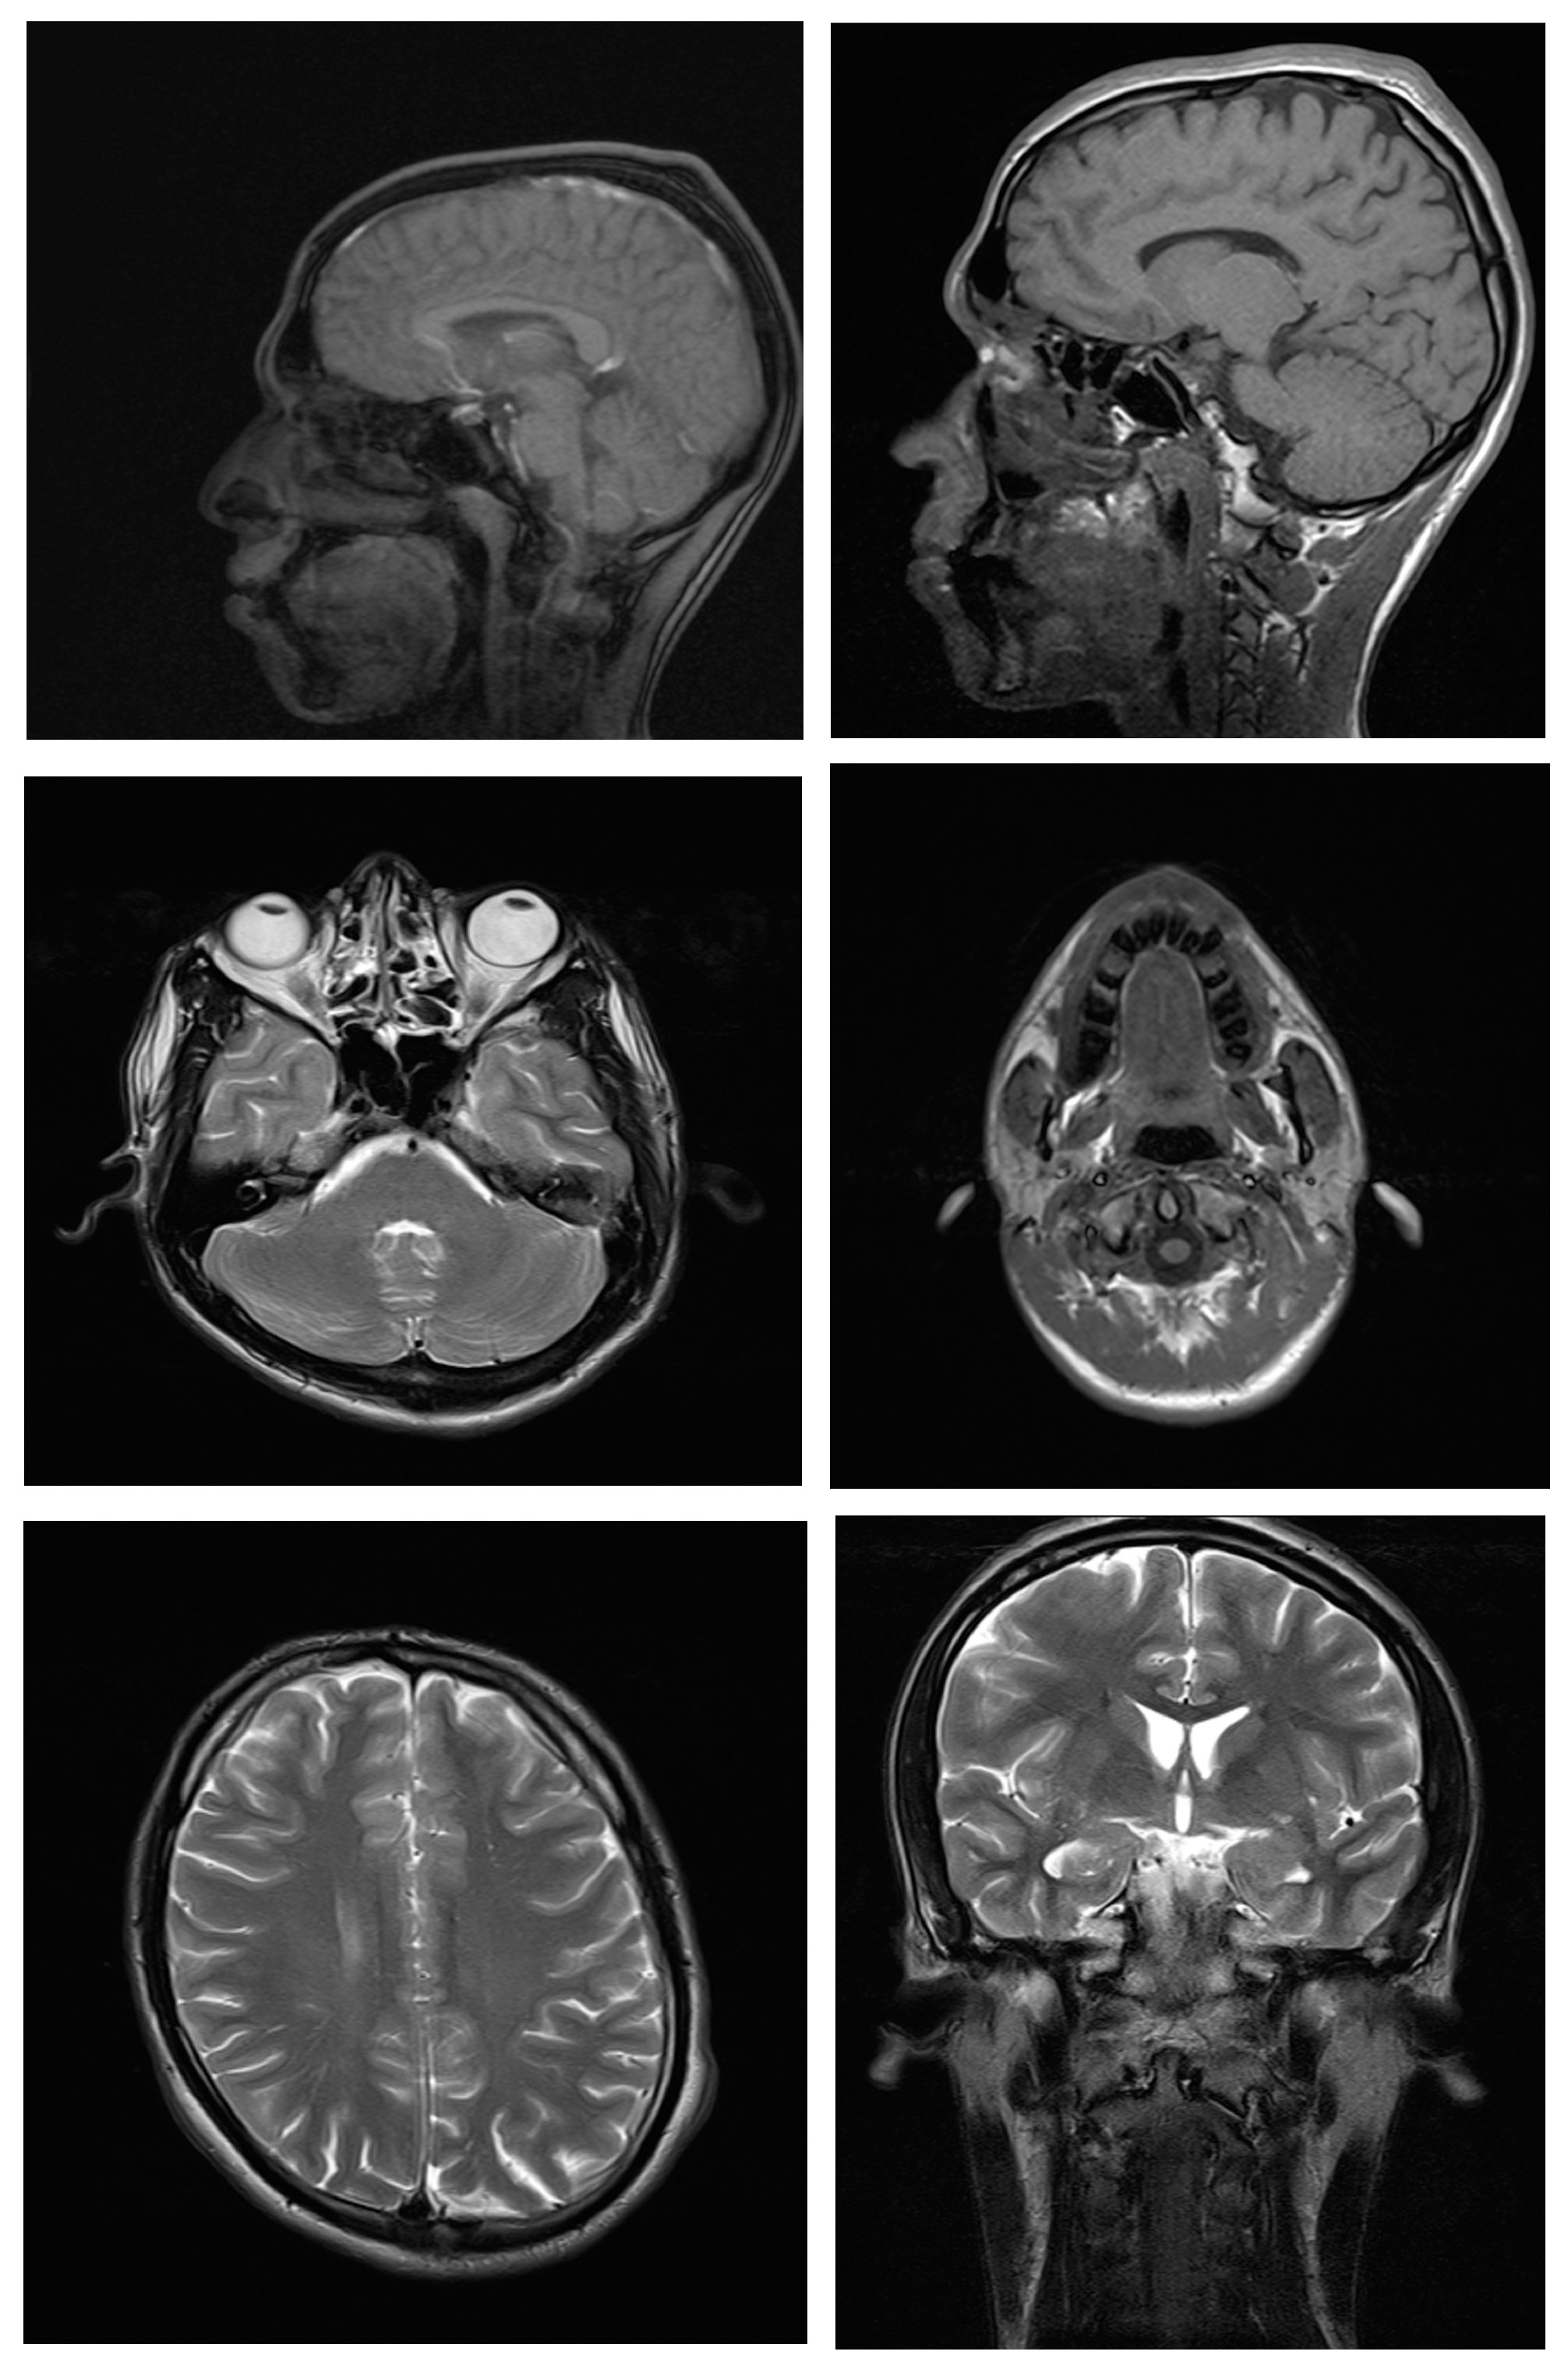

Magnetic resonance imaging scans were taken for all 38 subjects to study diagnostic image quality. Since the orthodontic appliances were securely bonded with orthodontic composite, there were no special precautions taken regarding the possible dislodgement and heating of the appliances, as previous studies had found changes in the temperature of the appliances to be clinically insignificant (within 1°C).16 The MRI scans for all types of bracket and retainer materials are shown in Figure 1, Figure 2, Figure 3, Figure 4, Figure 5, Figure 6, Figure 7, Figure 8, Figure 9, Figure 10. Non-diagnostic or unclear ROI are marked with arrows. None of the patients reported any discomfort or pain during MRI examination. The MRI scans were analyzed by a panel of 6 qualified and licensed radiologists, who assessed their diagnostic quality. The scans were compared with controls that included images from the archives of the Department of Radio-Diagnosis of Kamineni Institute of Medical Sciences. The radiologists ranked the images according to the distortion observed in the abovementioned ROI, using the modified receiver operating characteristic (ROC) analysis of distortion scoring system (Table 2), as described by Elison et al.17 In this method of distortion classification, a score of 3 represents the cut-off point for clinical usability. Images with a score of 3 have moderate distortion or artifacts, but they can still be used for diagnosis.

Ceramic self-ligating brackets with metal slots had a mean distortion score of 1.67 and mean distortion scores of 1.6 at all 6 anatomic sites except for the posterior cerebral fossa (1.0). This indicates minimal distortion for all ROI. Hence, the MR images taken with self-ligating brackets were diagnostic. A study conducted by Asano et al., in which 3 types of brackets (titanium, ceramic and ceramic with metal slots) were used in a single patient, concluded that the MR images showed little distortion and were interpretable.27 Since all 3 types of brackets were used in a single patient, one cannot distinguish their individual effects on the MRI scans.27

The mean distortion scores for ceramic and polycarbonate brackets were 1.00, and the mean distortion scores at all 6 anatomic sites were also 1.00, which implies no distortion for any ROI; hence, the MR images with ceramic and polycarbonate brackets were considered diagnostic.